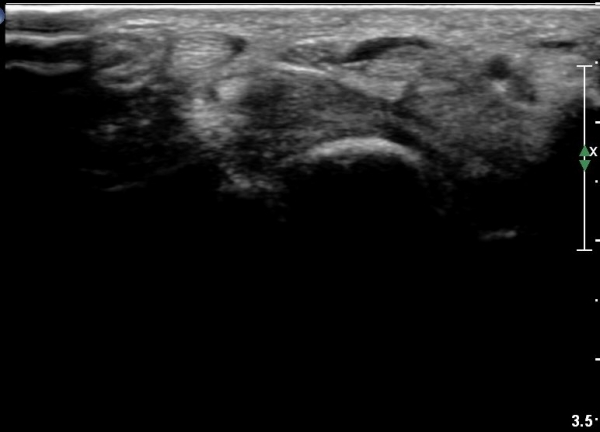

¼Õ¹Ù´Ú ±ÙÀ§ºÎ Ⱦ´Ü¸é°Ë»ç¿¡¼­ Á¤Á߽ŰæÀº ºÎÁ¾ µî ƯÀÌ ¼Ò°ßÀÌ º¸ÀÌÁö ¾ÊÀ¸³ª

¹«Áö±Ù °æ°èºÎ ̫̿¿¡ Àú¿¡ÄÚ Á¾¾çÀÌ °üÂûµÈ´Ù(»çÁø 4, 5).